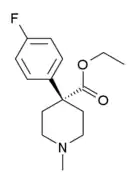

There are a number of broad classes of opioids:[260]

Phenylpiperidines

- Pethidine (meperidine)

- Ketobemidone

- MPPP

- Allylprodine

- Prodine

- PEPAP

- Promedol